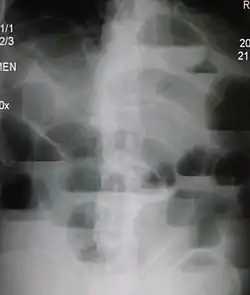

![]() Upright تصوير بالأشعة السينية للبطن demonstrating a small bowel obstruction. Note multiple air fluid levels. Upright تصوير بالأشعة السينية للبطن demonstrating a small bowel obstruction. Note multiple air fluid levels. | |